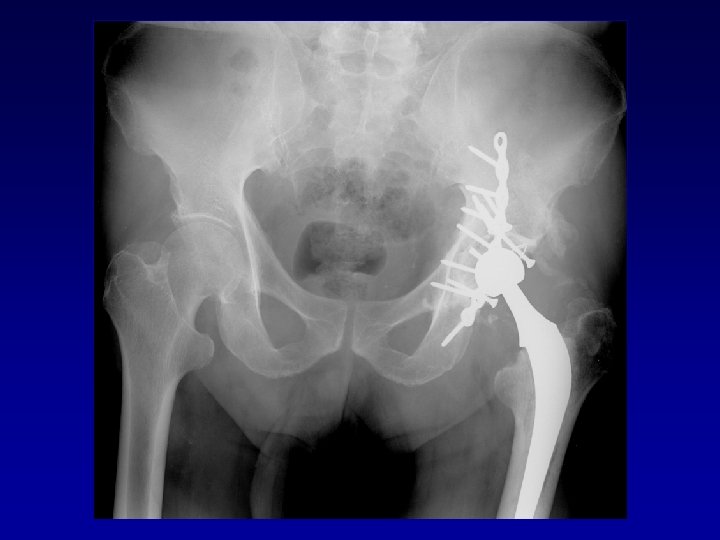

Arthroplastie totale de hanche sur fracture du cotyle complexe (LCH) • Voie d’abord par

Arthroplastie totale de hanche sur fracture du cotyle complexe (LCH) • Voie d’abord par TROCHANTEROTOMIE Libération de la fibrose, capsule, cicatrices • Permet : Exposition Récupération de la longueur Mobilité

Arthroplastie totale de hanche sur fracture du cotyle complexe Recentrage, reconstruction, orientation du cotyle

Arthroplastie totale de hanche sur fracture du cotyle complexe Recentrage, reconstruction, orientation du cotyle • • Greffe Ostéosynthèse par plaque MK Surtout si pseudarthrose Réduction de la luxation